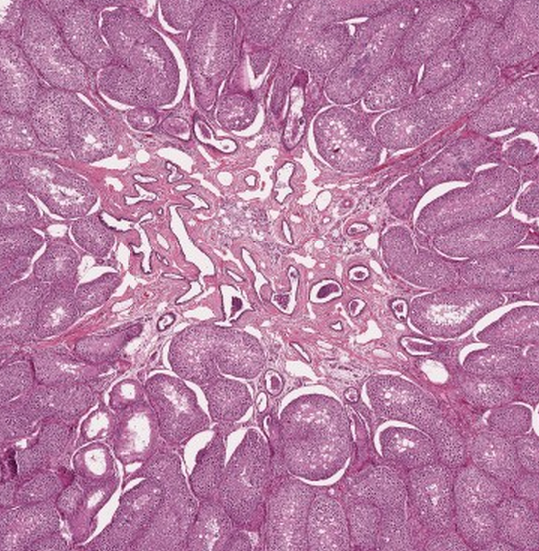

3

Q

What lymphatic organ is this? What are the arrows pointing to?

A

Thymus, Hassall’s corpuscles